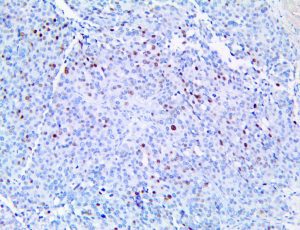

It is the ICU physician who is most likely to witness one of the deadliest manifestations of the abnormal immunological response, the cytokine storm syndrome (CSS). This response is also referred to by some as the cytokine release syndrome (CRS). CSS is characterized by continuous activation and expansion of macrophage and lymphocyte populations, which secrete large amounts of cytokines, causing the cytokine storm. This massive cytokine release is akin to hemophagocytic lymphohistiocytosis (HLH) disease, a syndrome characterized by initial unchecked and persistent activation of cytotoxic T lymphocytes and NK cells.

Clinical and laboratory manifestations of HLH include fever, enlarged liver and/or spleen, neurologic dysfunction, coagulopathy, liver dysfunction, cytopenias (i.e., low levels of erythrocytes, leukocytes, and/or platelets), hypertriglyceridemia, hyperferritinemia, hemophagocytosis, and eventually diminished NK cell activity as the immune system becomes progressively paralyzed. HLH can be familial (primary HLH) or secondary to another disease process (sHLH), such as rheumatic disease, in which it is referred to as macrophage activation syndrome (MAS, characterized by elevated ferritin).